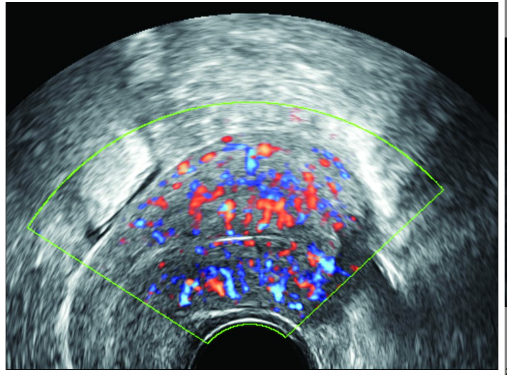

子宫内膜血流类型的评估:经阴道B超查看子宫内膜及子宫内膜下血流类型,采用Applebaum法分为三种分型:

I型:不能监测到子宫内膜血流;

II型:仅可监测到子宫内膜下血流;

III型:可监测到子宫内膜及子宫内膜下血流。

在这三种类别中,III型血流类型较其他类型更好,能让胚胎更好地着床。